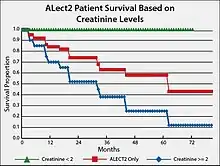

Based on studies conducted in the United States, the prognosis for individuals with ALECT2 is guarded, particularly because they are elderly and their kidney disease is usually well-advanced at the time of presentation.[17] End-stage renal disease develops in 1 out of 3 patients and has a median renal survival of 62 months.[10] A suggested prognostic tool is to track creatinine levels in ALECT2 patients. The attached Figure gives survival plotss for individuals with LECT2 renal amyloidosis and serum creatinine levels less than 2 mg/100 ml versus 2 mg/100 ml or greater than 2 mg/100 ml. The results show that afflicted individuals with lower creatinine levels have a ~four-fold higher survival rate.